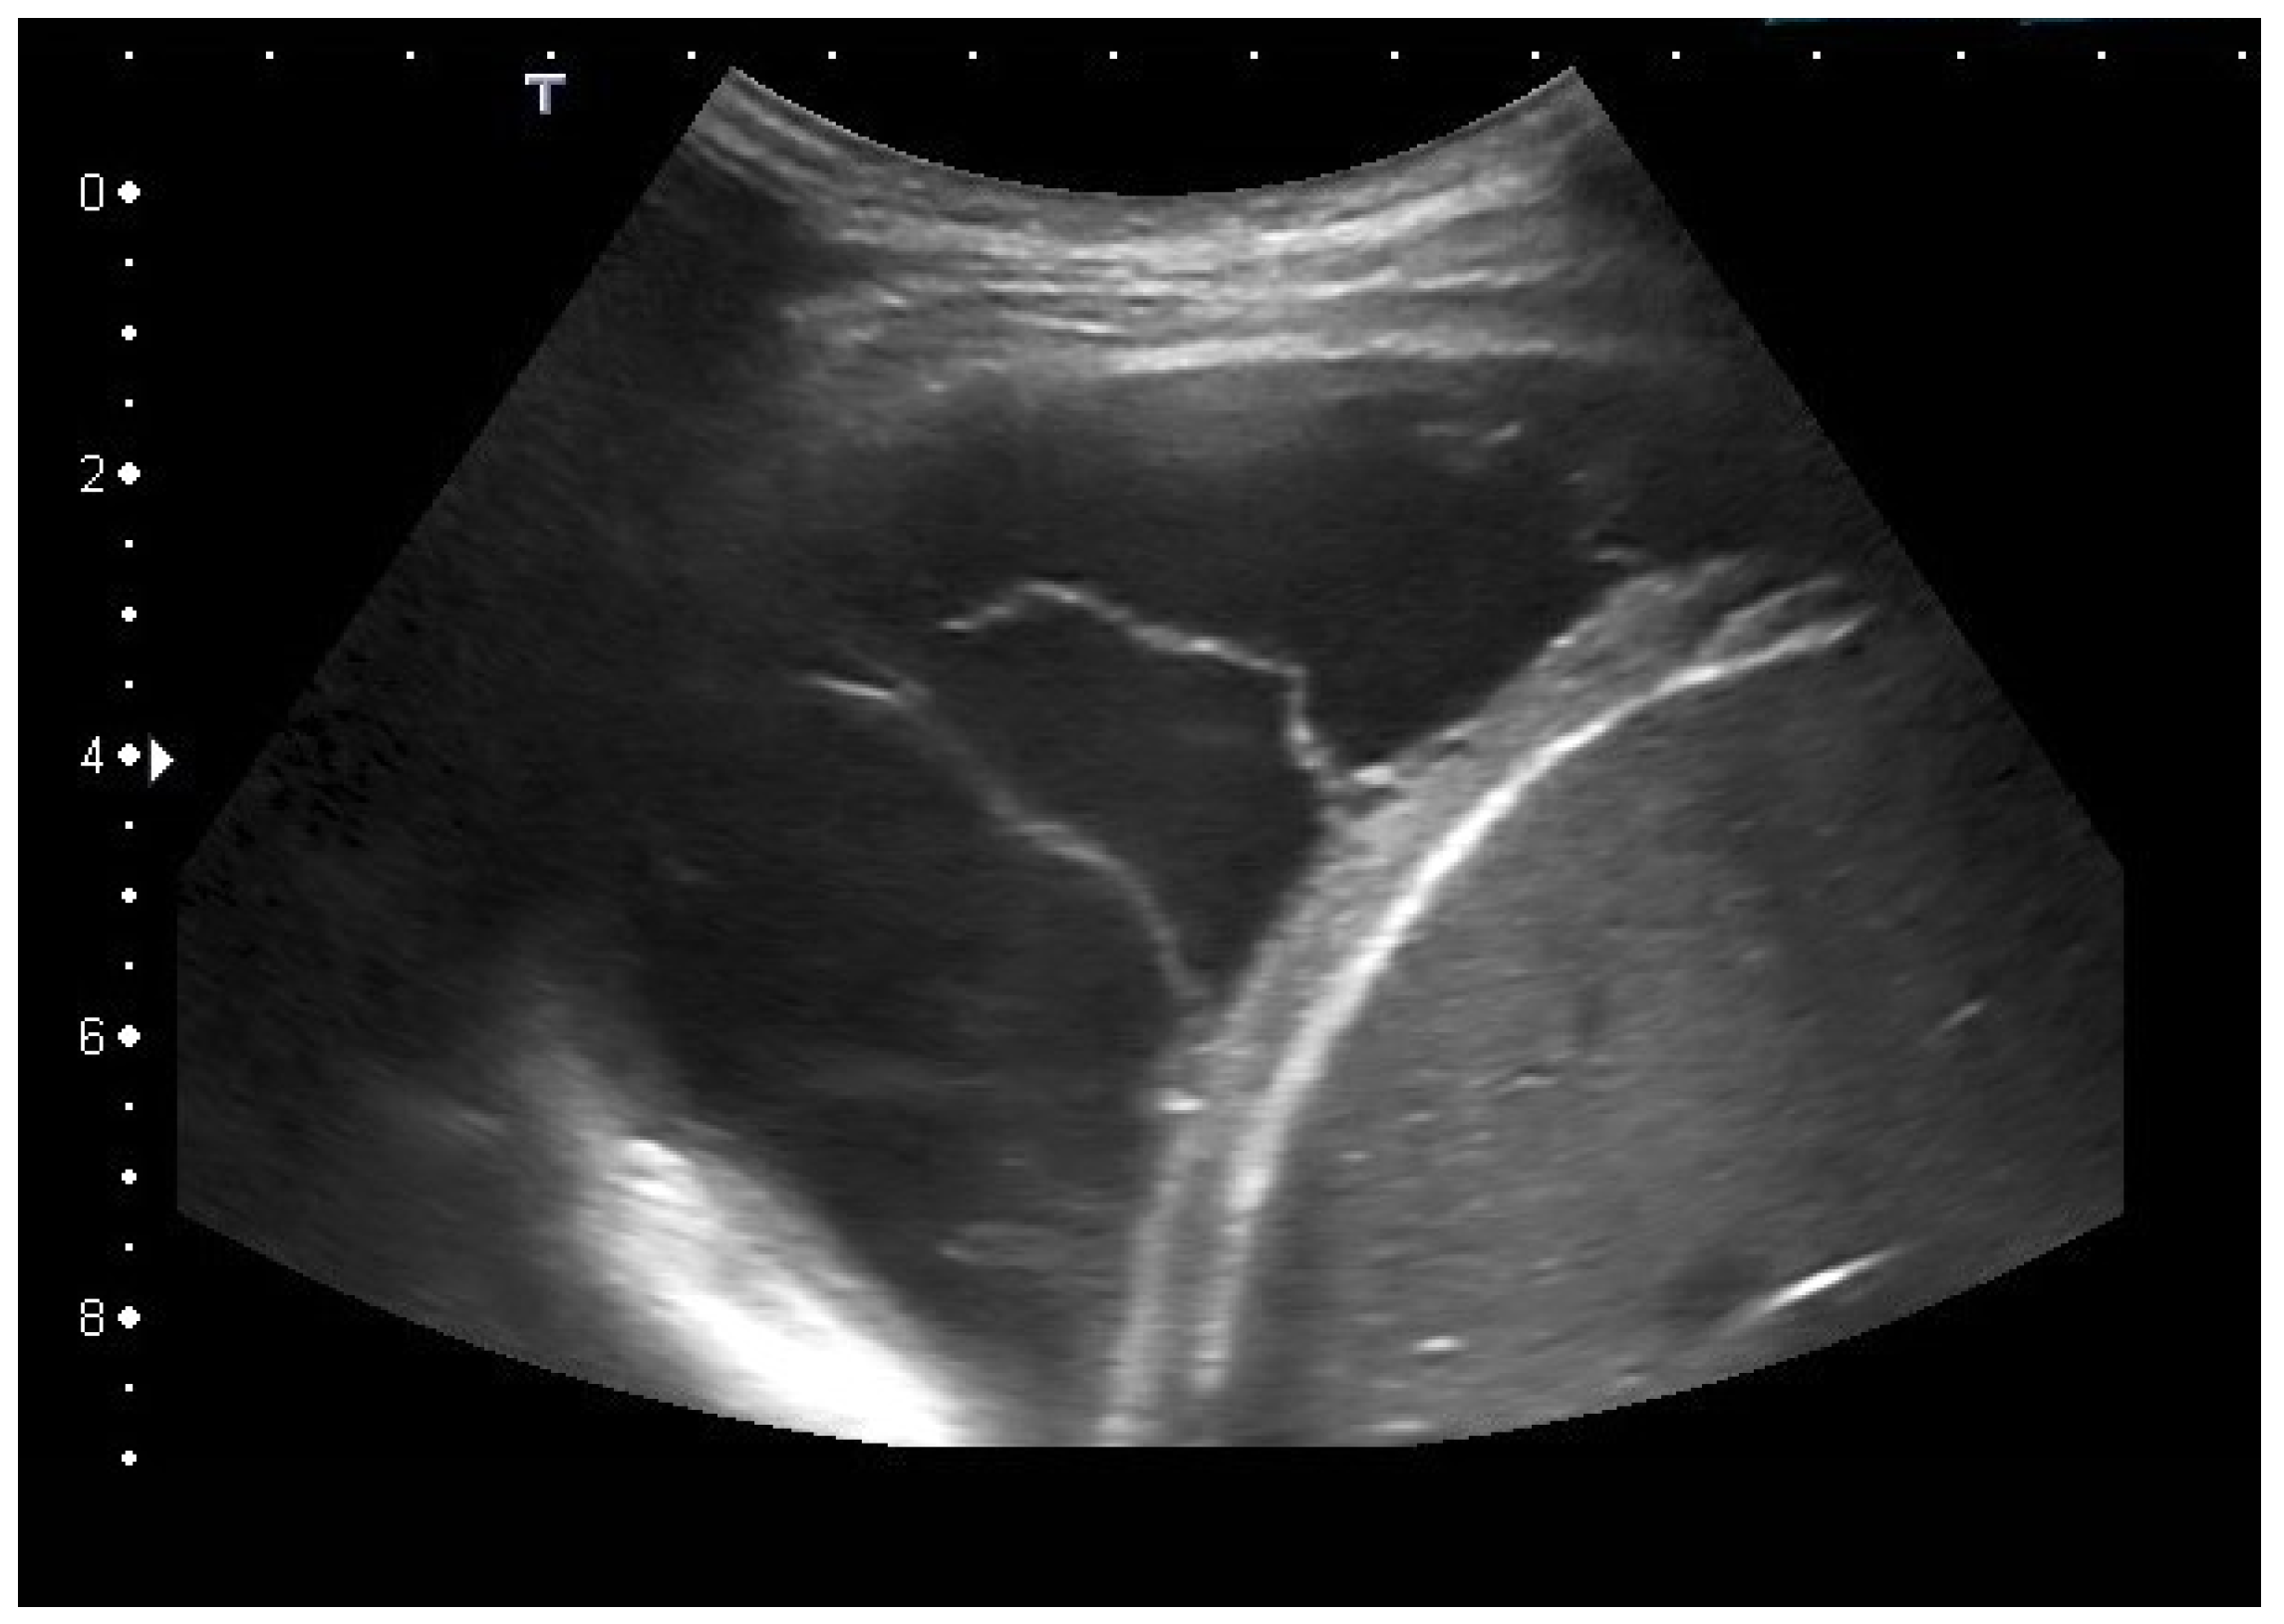

| Tuberculous pleuritis | Pleura effusion with fibrin strands, pleural calcification, and thickening. Hypoechoic granulomatous inflammation and granulomas with hyper-enhancement on CEUS in thickened pleura. Hypoechoic caseous abscesses in thickened pleura, hypo- or nonenhanced, heterogeneously enhanced lesions, with contrast-enhanced septations and contrast-enhanced rim. |